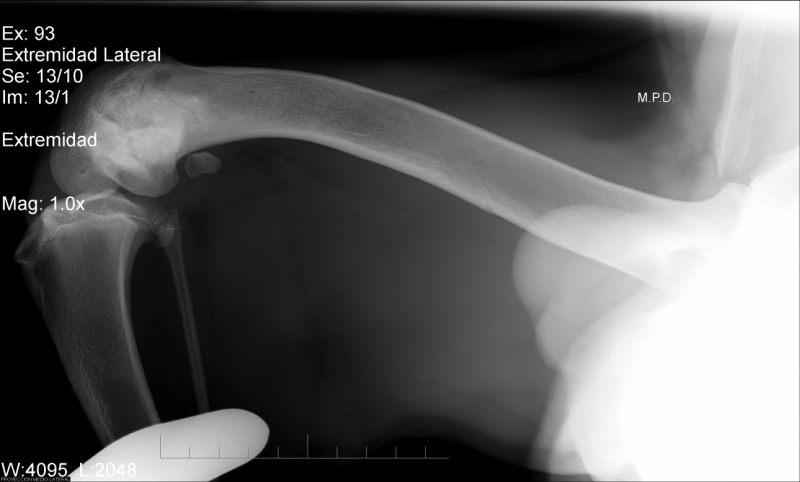

Pauvre Forest, il est handicapé, Forest se trouve actuellement dans notre refuge partenaire en Espagne. Forest aura besoin d interventions chirurgicales, mais il peut compter sur nous pour l’aider à retrouver une meilleure motricité. Il a une luxation bilatérale des rotules, grade 4, deux opérations seront nécessaires. Il sera donc placé en famille d’accueil en Espagne pendant une longue convalescence.